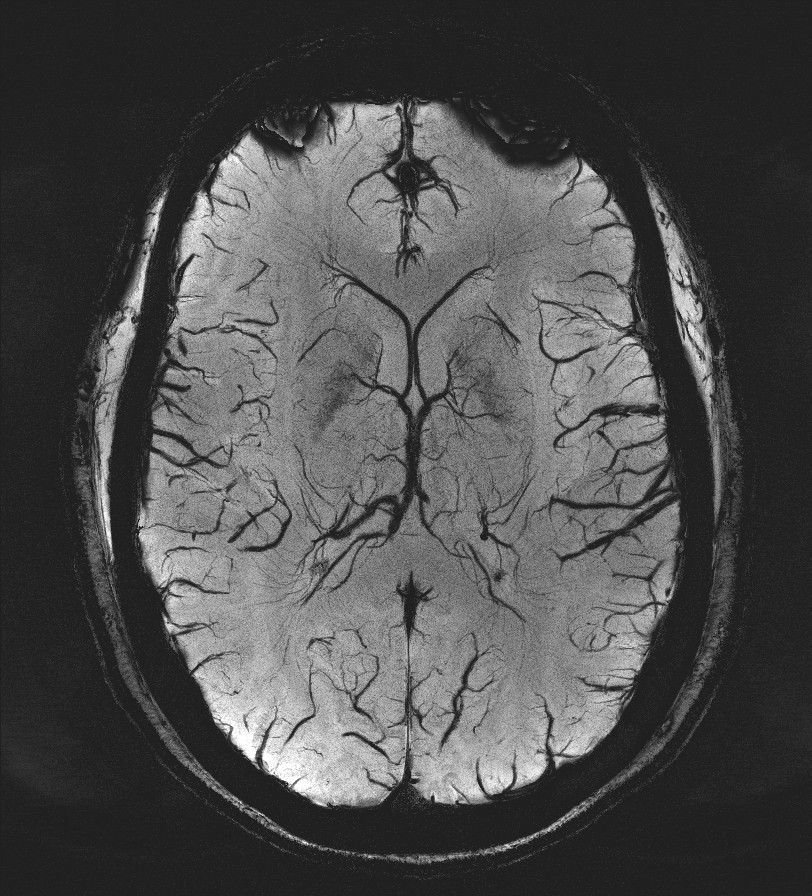

Susceptibility Weighted Image for Radiology

How it works: Susceptibility weighted imaging (SWI) is a non-invasive method of measuring susceptibility in the brain. The technique uses phase and magnitude information to generate an image which reflects the small changes in the local magnetic field. Certain substances such as iron or calcium cause local changes in the magnetic field which can be detected with great sensitivity. The technique does not require intravenous contrast and can be performed on patients of all ages. These techniques are most beneficial to patients with hemorrhages, trauma, concussion, amyloid angiopathy, venous thrombosis, vascular malformations, and tumors.

Benefits: SWI is non-invasive so it can be performed on any routine brain MRI on any patient regardless of intravenous access, contrast allergy, or renal status. Most OHSU MRI exams incorporate some form of susceptibility imaging including Gradient Recalled Echo (GRE), B0, or SWI. SWI is more sensitive than GRE imaging or the B0 images to detect small micro hemorrhages and small vessels. SWI is also able to determine if a structure is composed of calcium or blood based on the phase and magnitude information derived from the SWI.